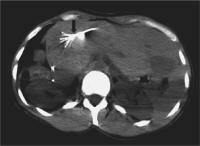

Abbildung 2: Axiale CT-Schicht nach i.v. KM-Gabe in der frühen portalvenösen Phase. Unmittelbar nach RFA Darstellung kleiner Gasbläschen und eines Perfusionsdefektes, der Nekrose entsprechend (dicker Pfeil). Der ablatierte Stichkanal ist gut zu erkennen (dünner Pfeil).